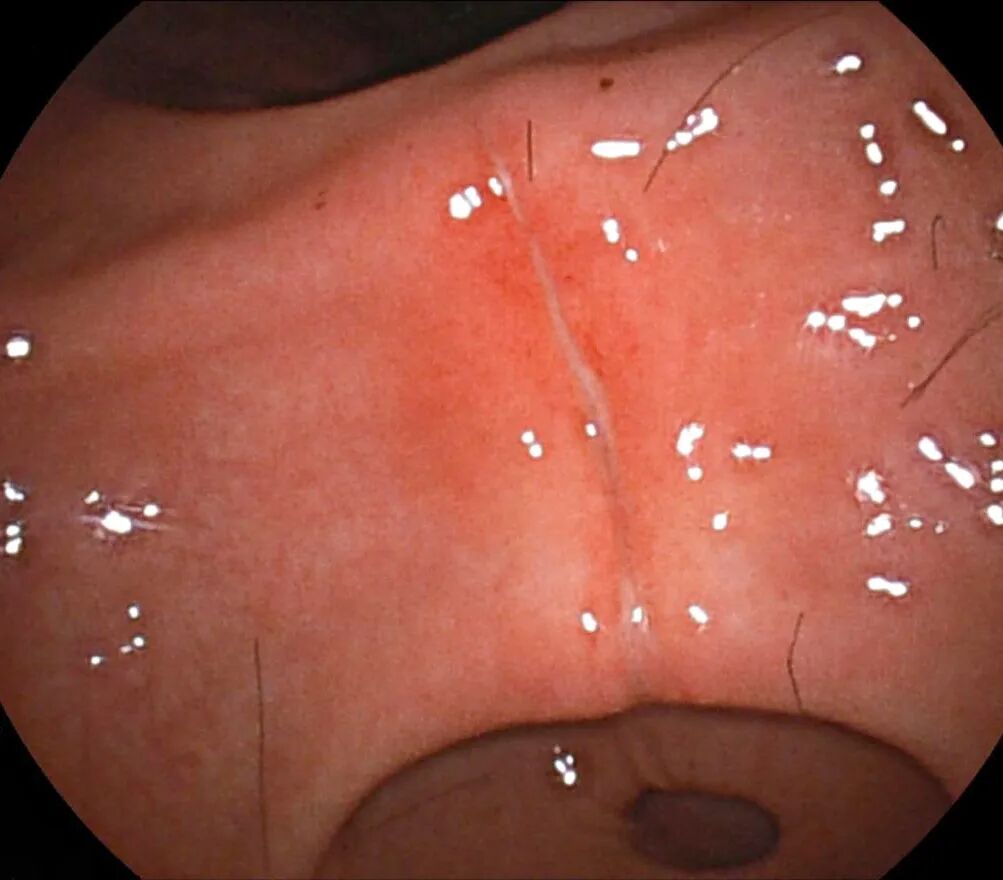

术后胃镜检查显示,除毛发团块长期摩擦导致的轻微糜烂外,小李的胃黏膜无其他损伤,未出现消化道出血、感染等并发症。

▲术后胃镜见些许糜烂